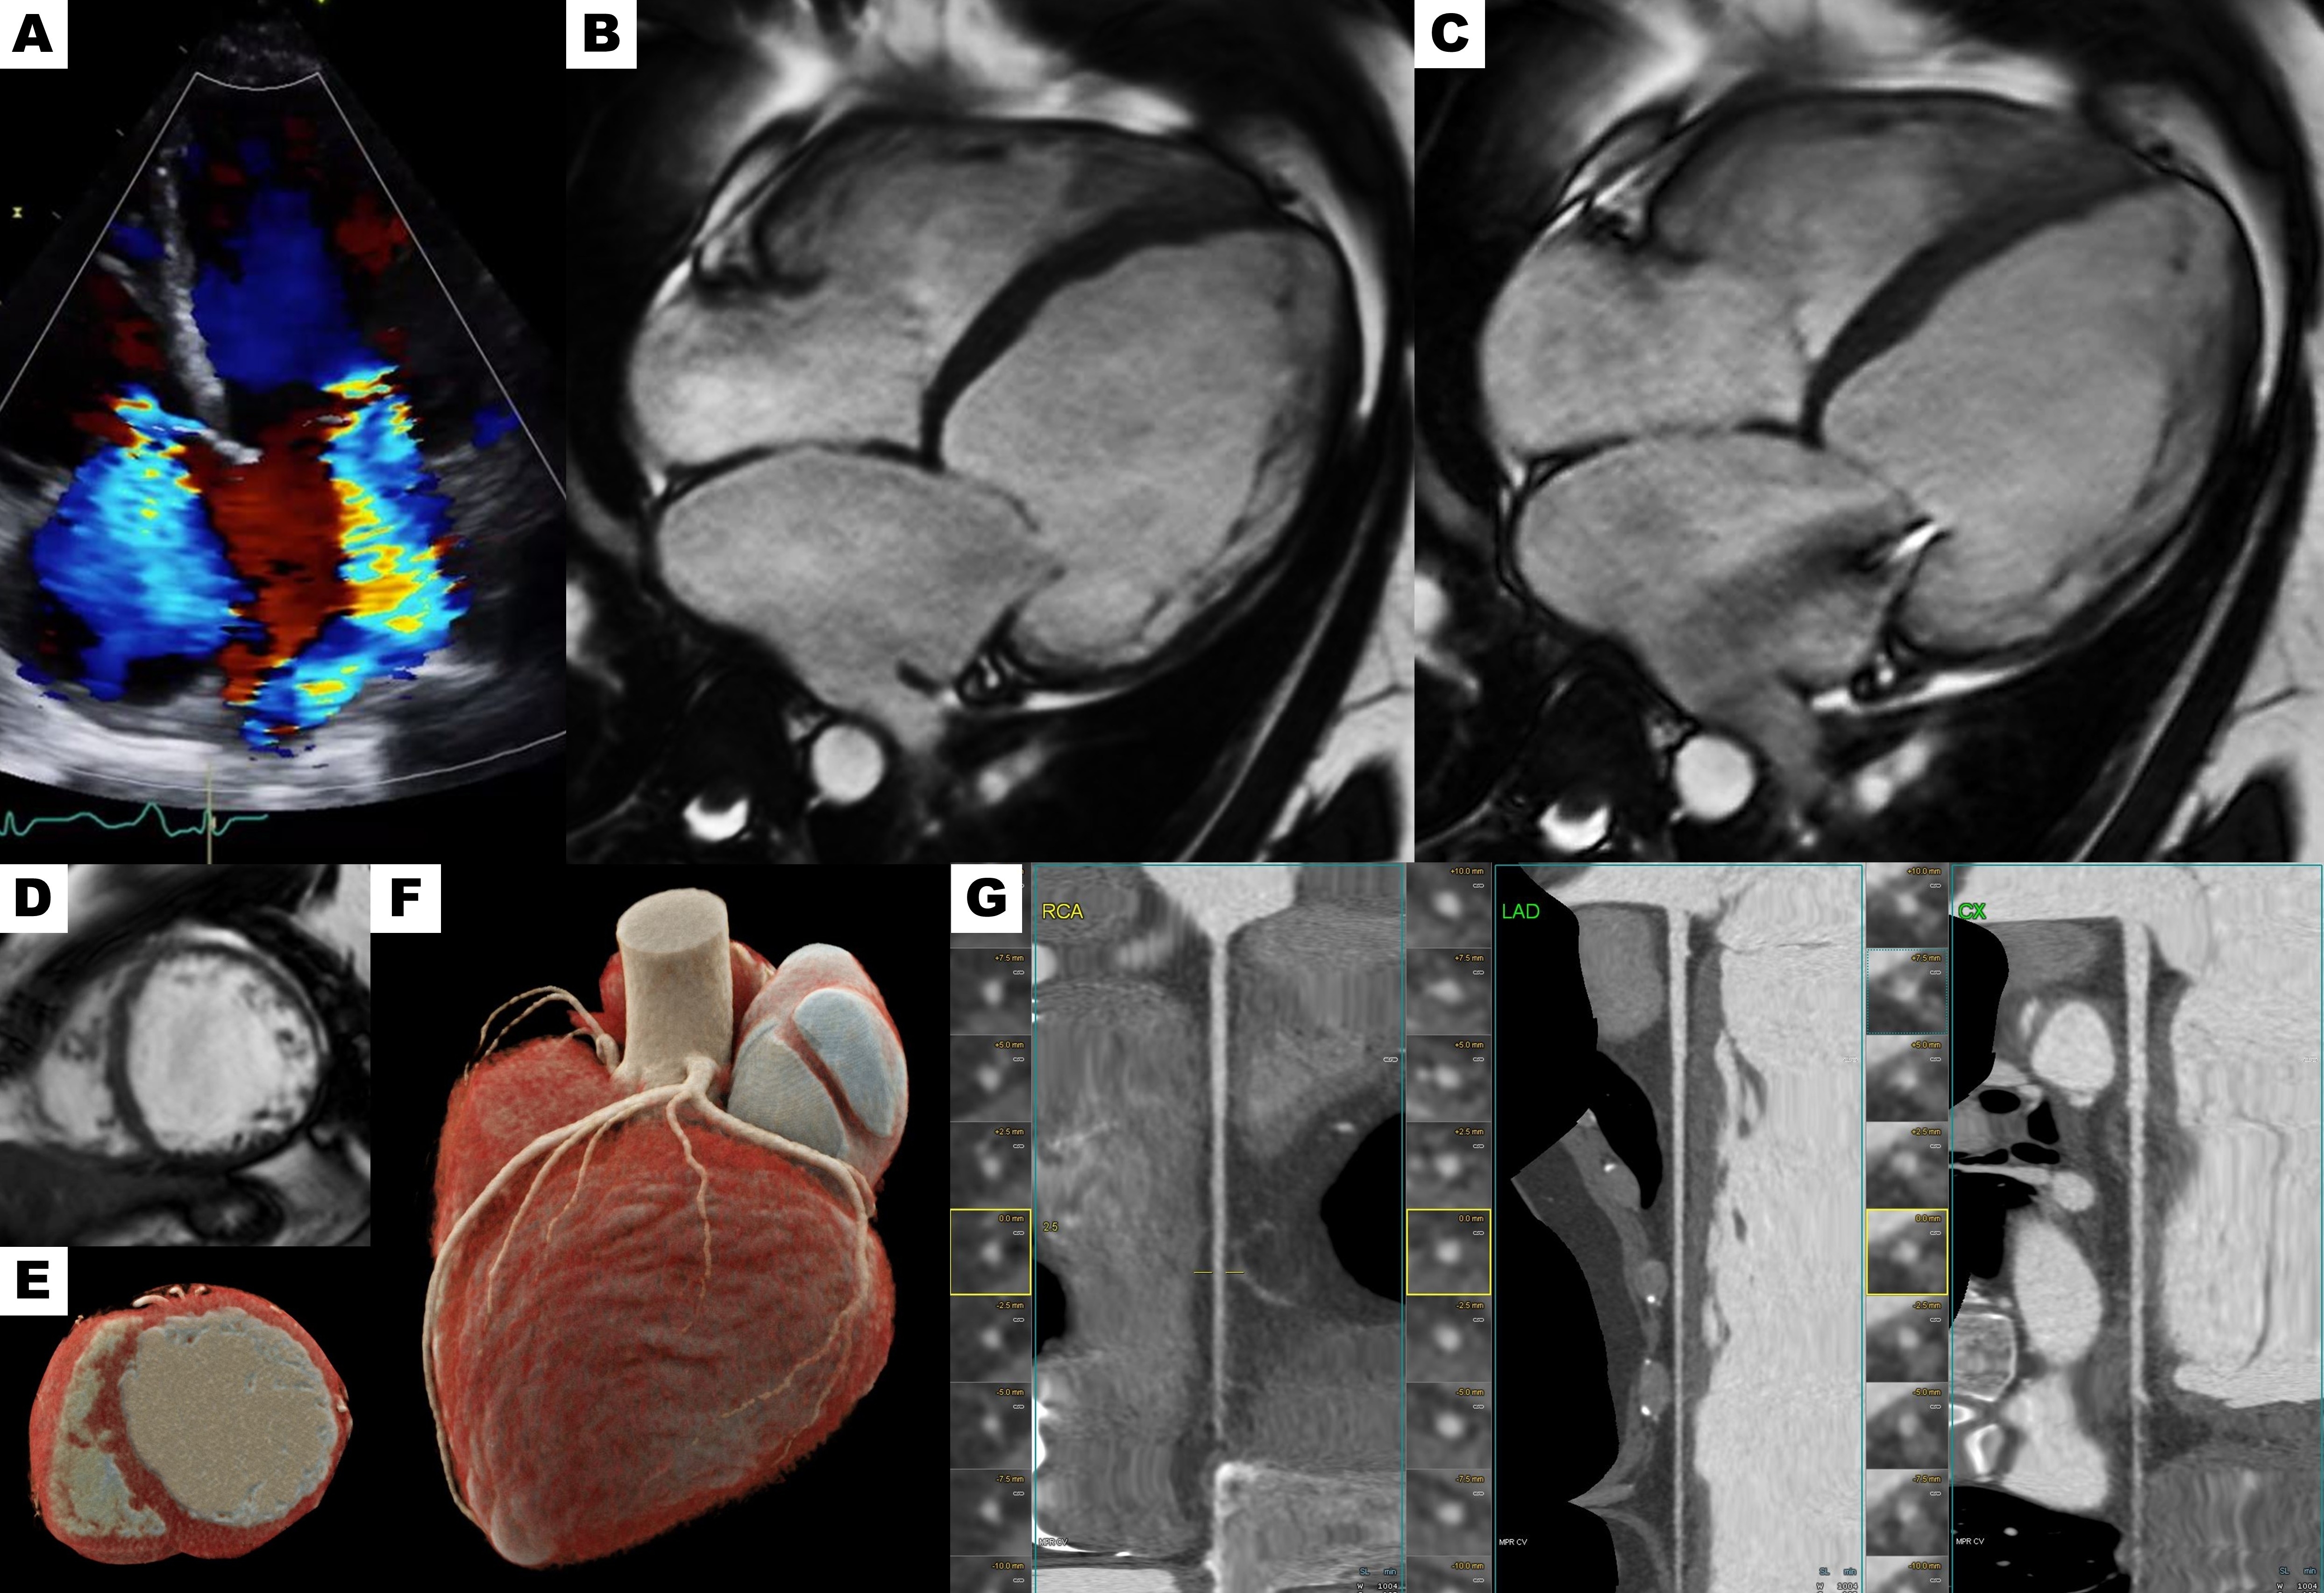

Figure 3. Myocardial strain evaluation with feature tracking technique. (A–B) Circumferential strain. (C–D) Longitudinal strain.